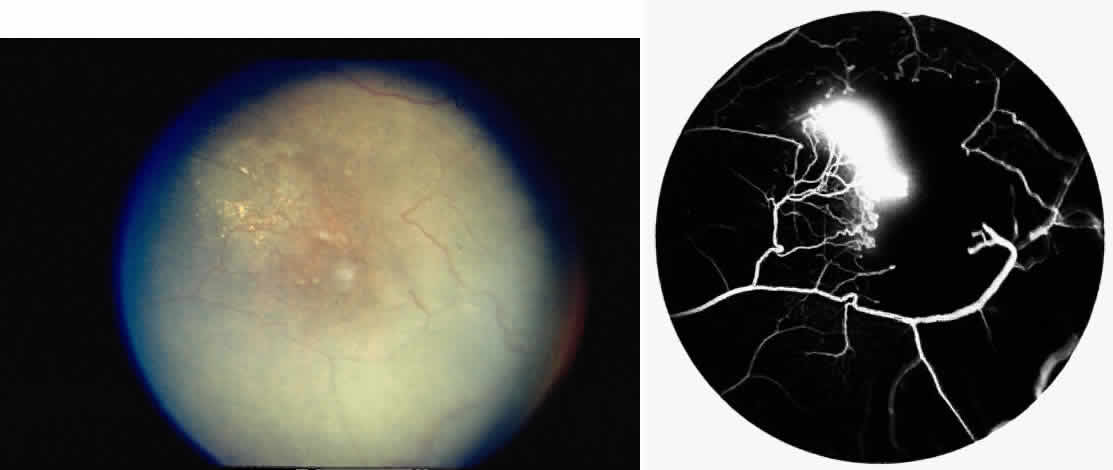

ANTERIOR SEGMENT

Conjunctival Sickle Sign

Abnormalities of the bulbar conjunctival blood vessels provide direct evidence of the vaso-occlusive process and were one of the earliest reported ocular changes.38–43 These abnormalities are believed to be the result of flow obstruction or impedance by sickled cells. The severity of the conjunctival changes ranges from linear dilatations to isolated groups of truncated, comma-shaped segments. These changes have been correlated with the ISC count, Hb S concentration, and the intraerythrocytic hemoglobin concentration (Fig. 1).44–47 Although they are known as the conjunctival sickle sign, these vascular abnormalities are not completely pathognomonic of sickle cell disease: in rare cases they are seen in patients with AIDS, chronic myelogenous leukemia, and other vaso-occlusive diseases.47–49

Fig. 1. Conjunctival vascular abnormalities in a patient with homozygous sickle cell anemia demonstrating interrupted, dilated, and truncated vascular segments.

Iris Atrophy and Neovascularization

Occlusions of the iris vessels can result in atrophy, and patients may present with asymptomatic white patches of the iris.50,51 The area of atrophy may be extensive (Fig. 2) and may be associated with pupillary irregularity. Iris neovascularization may develop in eyes with chronic retinal detachment or major arteriole occlusions and can in rare cases cause a secondary neovascular glaucoma.52

Fig. 2. Iris infarcts in a patient with SC disease (arrows).